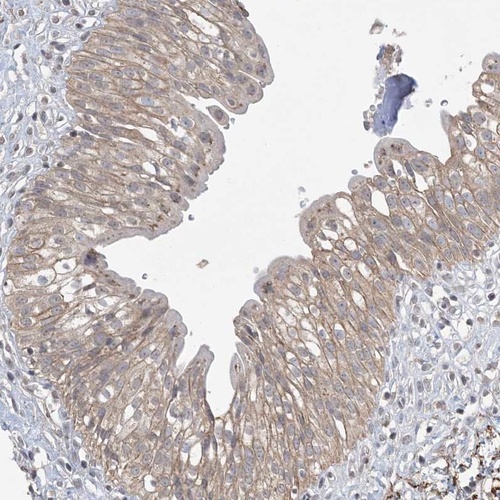

Immunohistochemical staining of human urinary bladder shows weak cytoplasmic positivity in urothelial cells.